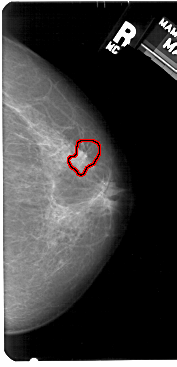

FILE: A_1520_1.RIGHT_MLO.OVERLAY

TOTAL_ABNORMALITIES 1

ABNORMALITY 1

LESION_TYPE CALCIFICATION TYPE PLEOMORPHIC DISTRIBUTION CLUSTERED

LESION_TYPE MASS SHAPE IRREGULAR MARGINS SPICULATED

ASSESSMENT 4

SUBTLETY 3

PATHOLOGY MALIGNANT

TOTAL_OUTLINES 1

BOUNDARY